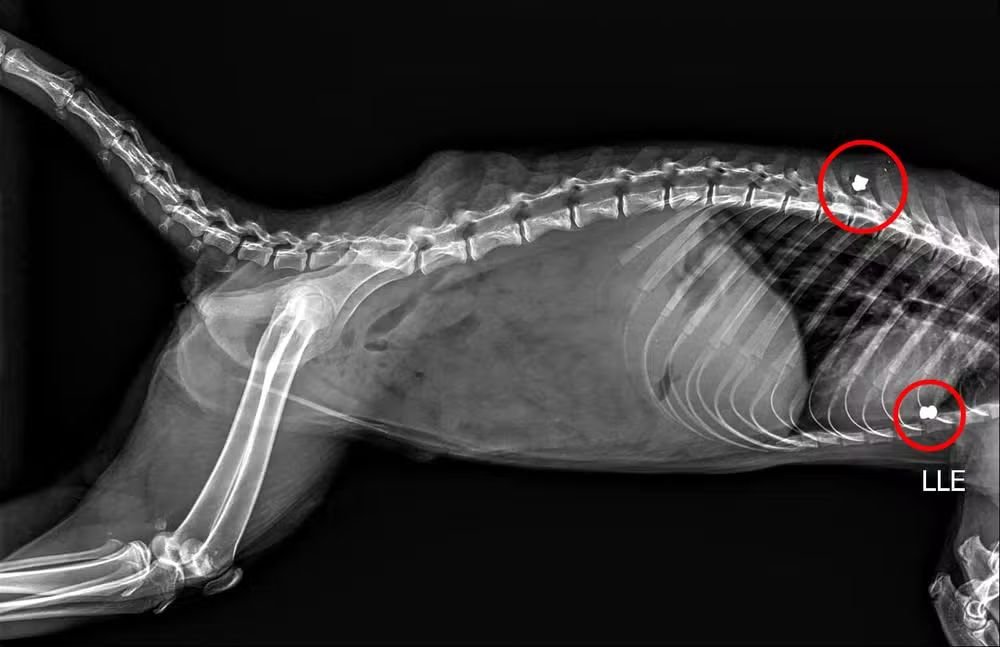

A Prefeitura de Marília (SP) emitiu um alerta sobre maus-tratos contra animais silvestres após um quati ser resgatado ferido por tiros de chumbinho no Bosque Municipal Rangel Pietraroia. O animal foi socorrido em 15 de abril pela Secretaria do Meio Ambiente e segue em atendimento veterinário especializado. Segundo a prefeitura, um raio-X mostrou dois chumbinhos alojados no corpo do quati.